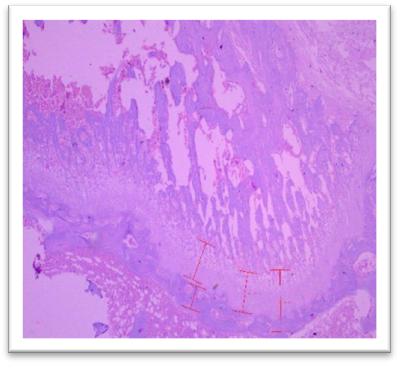

Histomorphometry

At the end of the study, femur bones were dissected and fixed for histological analysis. Group I (Normal) showed normal bone architecture, with well-organized chondrocytes. Group II (Lanthanum Carbonate only) maintained normal bone growth. Group III (Chronic Kidney Disease control) exhibited fibrocartilaginous changes, disorganized collagen, and impaired endochondral ossification, characteristic of Chronic Kidney Dosease. Groups IV (150 mg/kg), V (250 mg/kg), VI (500 mg/kg), and VII (750 mg/kg) demonstrated varying degrees of improvement in bone structure, with the highest dose (Group VII) showing the most significant restoration of normal bone architecture. Histomorphometry of bone: In Group III, designated as positive control for Chronic Kidney Disease, histomorphometric analysis of femur revealed significant fibrocartilaginous changes within the articular cartilage, characterized by an increased fibroblast, loss of chondrocyte organization, and disorganized collagen deposition. Furthermore, the growth plate exhibited a marked increase in the thickness of the hypertrophic zone, suggesting impaired endochondral ossification. Similar findings were observed by Saito et al. (2021) who observed that in Adenine-induced Chronic Kidney Disease, there was a reduction in bone minera density (BMD) throughout the body as well as in the femur Furthermore, micro- computed tomography (micro-CT) analysis revealed a decline in the microstructural integrity of the cortical bone, which contributed to diminished bone strength in both cortical and trabecular regions. Ferrari et al. (2014) reported that the bone microarchitecture in rats subjected to Adenine-induced renal failure exhibited significant alterations, characterized by a reduced trabecular number and an increased trabecular separation. Additionally, the presence of fibrosis was noted in the rats with Adenine-induced renal failure. Ni et al. (2018) performed a histomorphometry analysis and revealing that the bone mineral density (BMD) in the femurs of rats with Chronic Kidney Disease (CKD) was markedly lower than that observed in the control (CTL) group. Additionally, significant bone loss was evident in both cortical and trabecular bone parameters of the femurs.  Lanthanum Carbonate @150mg/kg, 250mg/kg, 500mg/kg and 750 mg/kg, histomorphometric analysis revealed very minimal to nearly absent fibroblast proliferation in the articular cartilage, characterized by the absence of fibroblast- like cells and well-maintained chondrocyte organization. Additionally, the growth plate exhibited moderate proliferation of the hypertrophic zone, indicating significant improvement in endochondral ossification compared to the positive control group (Group III) and lower-dose treatment groups. These findings suggest that the highest dose of Lanthanum Carbonate (750 mg/kg) may provide the most effective therapeutic benefits in mitigating bone-related pathological changes associated with Chronic Kidney Disease Yajima et al. (2018) demonstrated that Lanthanum Carbonate enhanced the mineralization of the periosteal surface, augmented bone mass within the intracortical resorption areas, and improved mineralization on the minimodeling surface at the endocortical region. They concluded that Lanthanum Carbonate has the potential to bolster cortical stability in patients with Chronic Kidney Disease (CKD)..

Fig. 26 Group III femur, showing fibrocartilaginous changes, fibroblasts, loss of chondrocyte organization, and disorganized collagen deposition at articular cartilage. Increased thickness of the hypertrophic zone in the growth plate